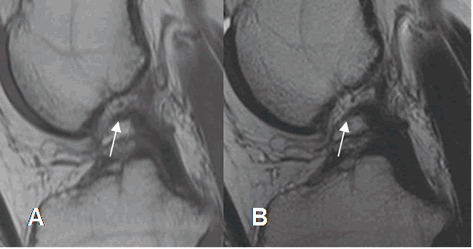

Fig 115. Fibrosis del LCP.

A: RM sagital en T1 y B: RM sagital en T2. El LCP está engrosado y con alteración de la señal, por fibrosis residual.

Fig 116. Lesión crónica reagudizada del LCP.

A: RM sagital en T1, B: RM sagital en T2 y C: RM coronal en STIR. Engrosamiento del LCP, por fibrosis reparativa. Existe zona hiperintensa en T2 y STIR, por reagudización.